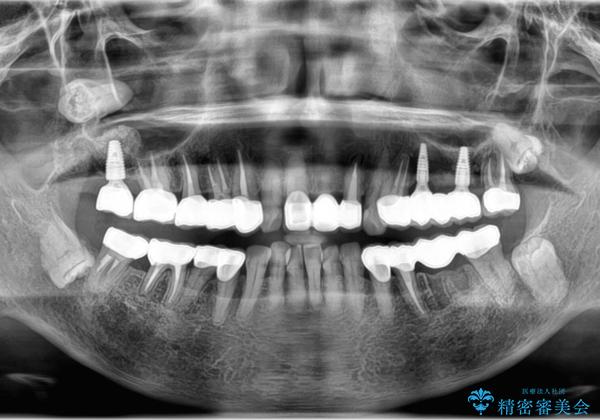

- 見た目の悪い銀歯や虫歯、歯の欠損、全体的な治療を希望されて来院されました。

インプラント治療や根管治療・セラミック治療を総合的に考えた精度の高い治療を計画し、しっかり噛めるようになるのはもちろん長期的な予後や審美性の向上を考えた全顎的な治療を実践していきます。

期間は約2年ほどかかりましたが、審美的な仕上がりとともに清掃のしやすさも非常に満足いただくことができました。